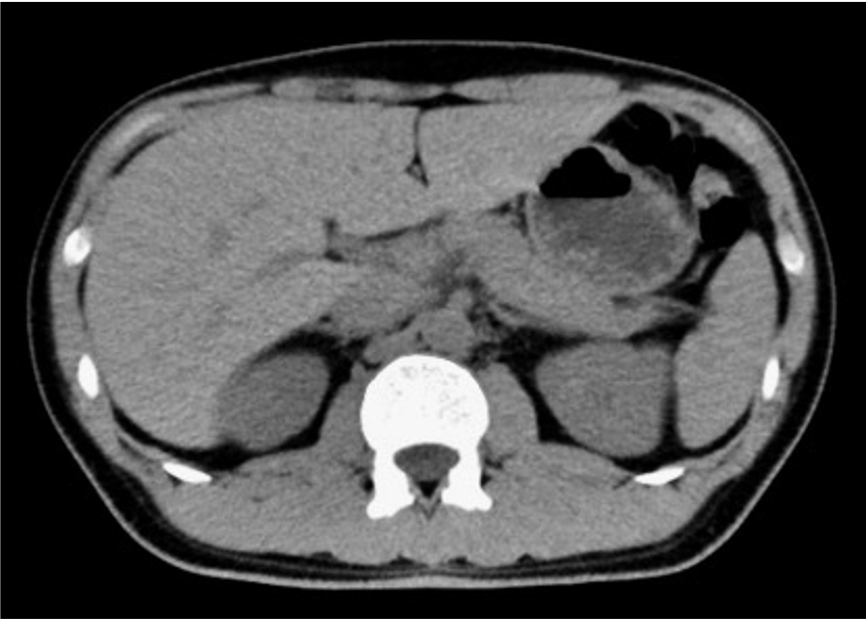

消化酵素を溜めている袋(胆のう)の中に何らかの原因でできた石を胆石と呼び、胆嚢の中に石があることを胆のう結石といいます。検診などで見つかることも多く、無症状の場合には経過を観察することもありますが、石が胆管に詰まると胆のう結石症を発症します。その症状は、みぞおちの右側を中心とした激しい痛みが典型的で、右肩や背中の痛みを伴う場合もあります。血液検査や腹部CT検査などで診断し治療方針を決めていきます。